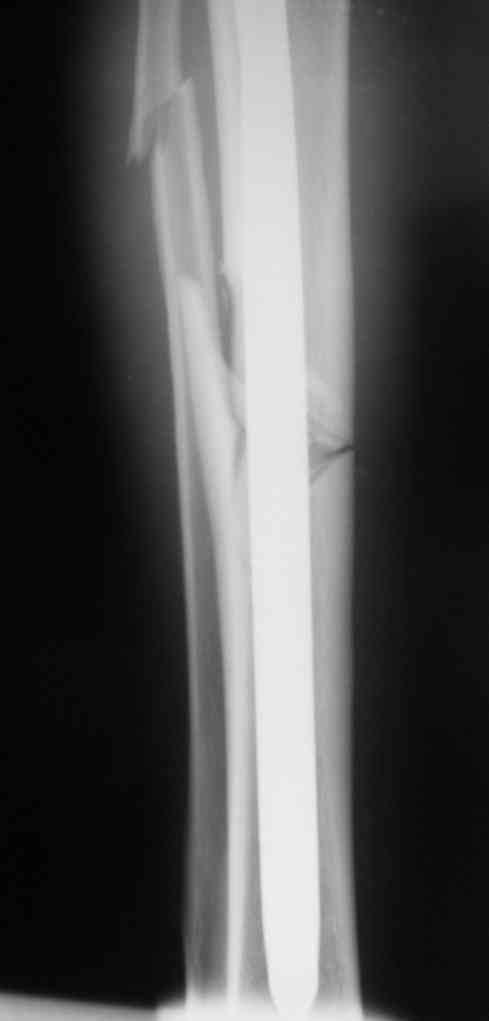

Дорогой Александр. Имею скромный опыт использования системы Fixion при переломах плеча, бедра и тибии. Всего 18 наблюдений с сентября 2006 г. Результаты отличные. Гвоздь индивидуален для каждого медуллярного канала. Легко имплантируется как в узкий, так и в деформированный канал. Это позволяет применять метод интрамедулярного остеосинтеза без ненужных потерь времени операции, флюороскопии и реально снижает крвопотерю и операционный риск. Удаление происходит без проблем. Особенно интересны больные с ипсилатеральными переломами бедра и голени.

В отношении ранней нагрузки при спиральных переломах лучше не торопиться. По данному случаю необходимо достигнуть исчезновения щели между штифтом и внутреним кортексом по Rg. А так картинка прекрасная - и длина сегмента и репозиция. Можно поздравить, коллега!

Да, спасибо за интересные иллюстрации. Получилось очень симпатично. На большеберцовой кости непременно надо было винты? Там же был торцовый упор, перелом в средней трети?